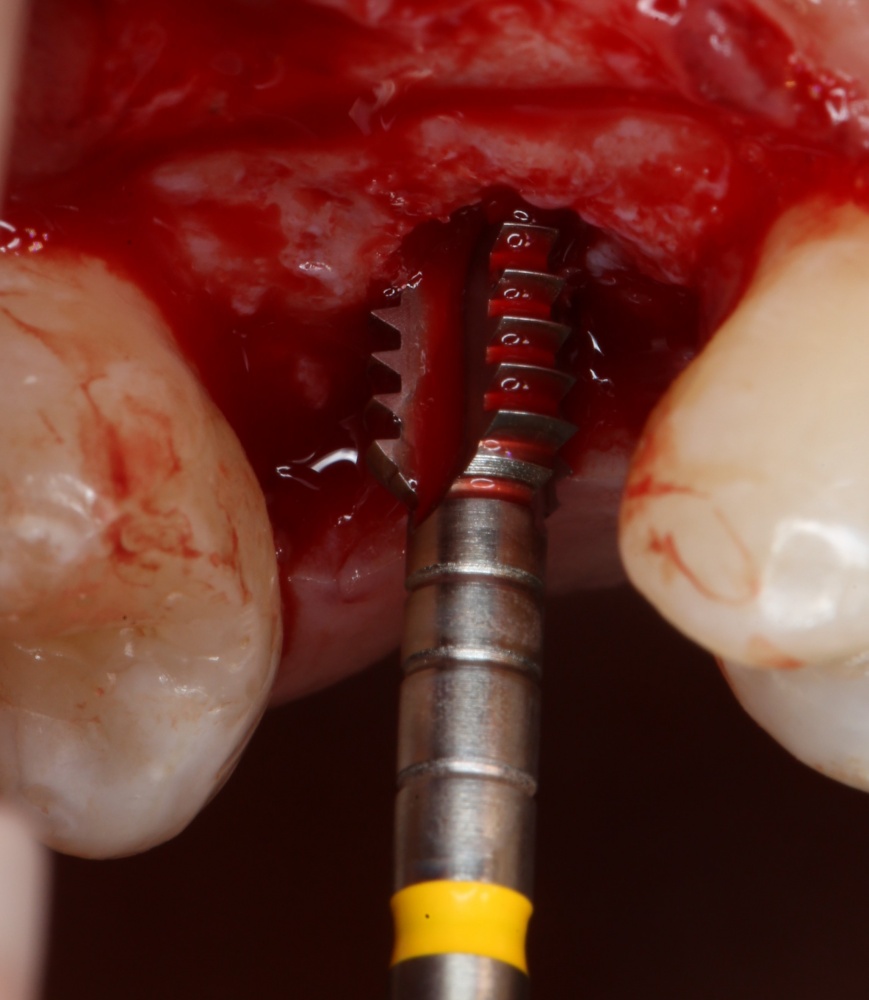

Подготовка лунок для имплантатов

Прежде, чем приступить к аугментации (пластике) лунок зубов, мы подготовили лунки для имплантатов. В таких клинических случаях нет необходимости в использовании шаблона. Вместо этого, мы применяем общепринятые правила позиционирования и соблюдаем рекомендации производителя по хирургическому протоколу:

В процессе ирригации лунки промываются, что позволило нам еще раз подтвердить ранее сделанные выводы. С помощью аналогов имплантатов, входящих в хирургический набор Xive, мы проверили возможность стабилизации имплантатов в будущих лунках. Исходя из правил подбора и позиционирования имплантатов (я очень рекомендую почитать об этом здесь>>) мы остановились на Xive S диаметром 3,4 мм и длиной 13 мм.

Подготовка двух лунок для имплантатов занимает около 10 минут.

Трансплантация десны, аугментация лунки

Для определения размеров будущего мягкотканного аутотрансплантата мы использовали пародонтологический зонд. С помощью него мы выбрали донорскую зону (бугор верхней челюсти или небная сторона альвеолярного отростка верхней челюсти в области моляров), с помощью скальпеля получили необходимый по размеру аутотрансплантат (мягкотканный лоскут для пересадки).

Затем, мы подготовили ксенографт Bio-Oss Collagen. Обычно на 2 зуба (центральных резца) с избытком хватает 100-миллиграмовой упаковки. Имеющийся в ней параллелепипед мы поделили на 2 усеченные пирамиды с основанием в 2/3 ширины изначального блока.

Если вы когда-нибудь видели подобные операции, то наверняка обращали внимание на порядок действий — сначала устанавливаются имплантаты, затем укладывается графт и только потом фиксируется мягкотканный аутотрансплантат. Для удобства в этом и похожих клинических ситуациях мы поменяли порядок действий:

Сначала мы провели и зафиксировали деэпителизированный соединительнотканный аутотрансплантат (ССТ). Для этого мы сформировали тоннель и использовали ортодонтическую проволоку в качестве проводника. Подробнее об этой методике можно почитать здесь>>.

Затем уложили ксенографт. Особенностями Bio-Oss Collagen являются удобство адаптации, устойчивость к вымыванию и выдавливанию, поэтому мы просто уложили полученные ранее пирамидки вестибулярно относительно будущего имплантата, после чего прижали их с помощью уже упоминавшихся аналогов имплантата, входящих в хирургический набор имплантационной системы Xive (кстати, при работе с другими имплантационными системами для паковки графта в лунке можно использовать круглые остеотомы для синуслифтинга).

В совокупности, аугментация лунок перед установкой имплантатов занимает около 20 минут — и это самый долгий из всех хирургических этапов лечения.